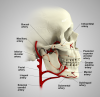

Vascularity in Different Regions of the Oral Cavity

Because major arteries and veins are located deep within the connective tissue of the oral cavity they typically are not damaged during routine dental surgical procedures.17,18 Nonetheless, to understand various bleeding scenarios that may be encountered when performing such surgical procedures, clinicians must be cognizant of the various blood vessels that potentially can be damaged (Figure 2).

Blood supply to the mandible: The external carotid artery gives off blood vessels in the neck, specifically the lingual and facial arteries. The lingual artery provides the sublingual artery that is found coronal to the mylohyoid muscle, and the facial artery supplies the submental artery, which is located inferior to the mylohyoid muscle. These vessels provide vascularity to the floor of the mouth and the tongue. The lingual gingiva derives blood supply from the sublingual artery, and the buccal gingiva gets its vascular supply from the buccal artery.

Vascularity in the maxilla: The external carotid artery gives rise to the maxillary artery, which provides a variety of branches important to the dental surgeon. In the palate, the greater palatine artery emerges from the greater palatine foramen and courses anteriorly in the groove located between the horizontal and vertical walls of the palatal vault, and the nasopalatine artery emerges from the nasopalatine foramen lingual to the maxillary incisors. The lingual gingival tissues receive vascularity from palatal vessels, and the buccal gingiva is supplied by the buccal artery and the posterior, middle, and anterior superior alveolar arteries.